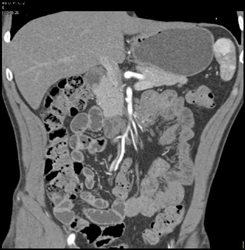

Splenic Hemangiomas